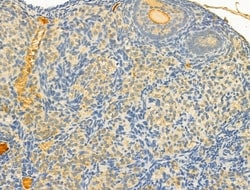

Invitrogen™ TOMM40 Polyclonal Antibody

Antibody detects endogenous levels of total TOM40.

| Immunohistochemistry (Paraffin), Western Blot | |

| A synthesized peptide derived from human TOMM40(Accession O96008), corresponding to amino acid residues R173-Q223. | |